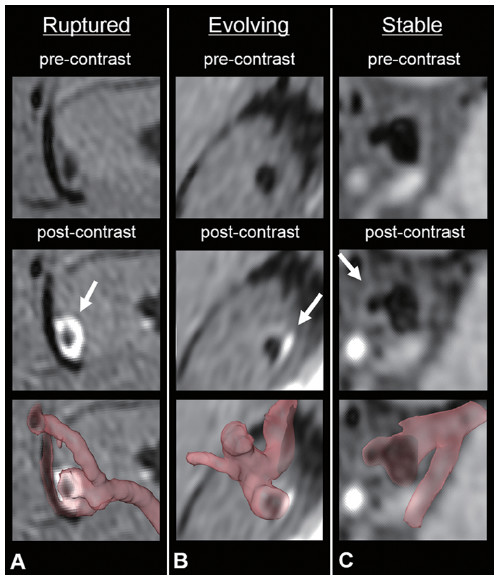

32. 磁共振血管壁成像对于进展期颅内动脉瘤出现瘤壁环形强化的研究

Circumferential wall enhancement in evolving intracranial aneurysms>Author: Shunsuke Omodaka, Hidenori Endo, Kuniyasu Niizuma, Miki Fujimura, Takashi Inoue, Toshiki Endo, Kenichi Sato, Shin-ichiro Sugiyama and Teiji Tominaga

DOI: https://doi.org/10.3171/2018.5.JNS18322

最新的MR血管壁成像研究表明,处于活动期的颅内动脉瘤可以出现瘤壁环形强化(CEAW)。虽然破裂动脉瘤经常表现出CEAW,但处于进展期(即生长期或症状期)的未破裂动脉瘤是否也有CEAW尚无详细研究。本文作者通过定量比较评估进展期未破裂动脉瘤、稳定期未破裂和破裂动脉瘤中的CEAW对这一问题进行阐述。通过MR血管壁成像技术对26例处于进展期的未破裂动脉瘤进行CEAW定量分析。在注射对比剂之前和之后分别获得三维T1加权的快速自旋回波序列成像,以脉瘤壁与垂体柄的MR对比度作为CEAW数值(CRstalk)。将这26例动脉瘤特征与69例稳定期未破裂动脉瘤和67例破裂动脉瘤进行比较研究。结果显示:进展期动脉瘤的CRstalk值显著高于稳定期动脉瘤的CRstalk值(0.54vs.0.34,p<0.0001),并低于破裂动脉瘤(0.54vs0.83,p<0.0002)。在多因素分析中,进展期未破裂动脉瘤的CRstalk值与稳定期未动脉瘤之间有显著差异(优势比12.23,95%置信区间3.53-42.41),与破裂动脉瘤比较亦差异明显(优势比0.083,95%置信区间0.022–0.310)。该研究表明进展期未破裂动脉瘤的CEAW高于稳定期未破裂动脉瘤的CEAW,且低于破裂动脉瘤的CEAW值。作者指出 CEAW的变化可能反应了颅内动脉瘤从未破裂到破裂的过程,今后也许可以作为未破裂动脉瘤需要手术干预的指标。

图:破裂动脉瘤,进展期未破裂动脉瘤及稳定期未破裂动脉瘤的MR增强表现。